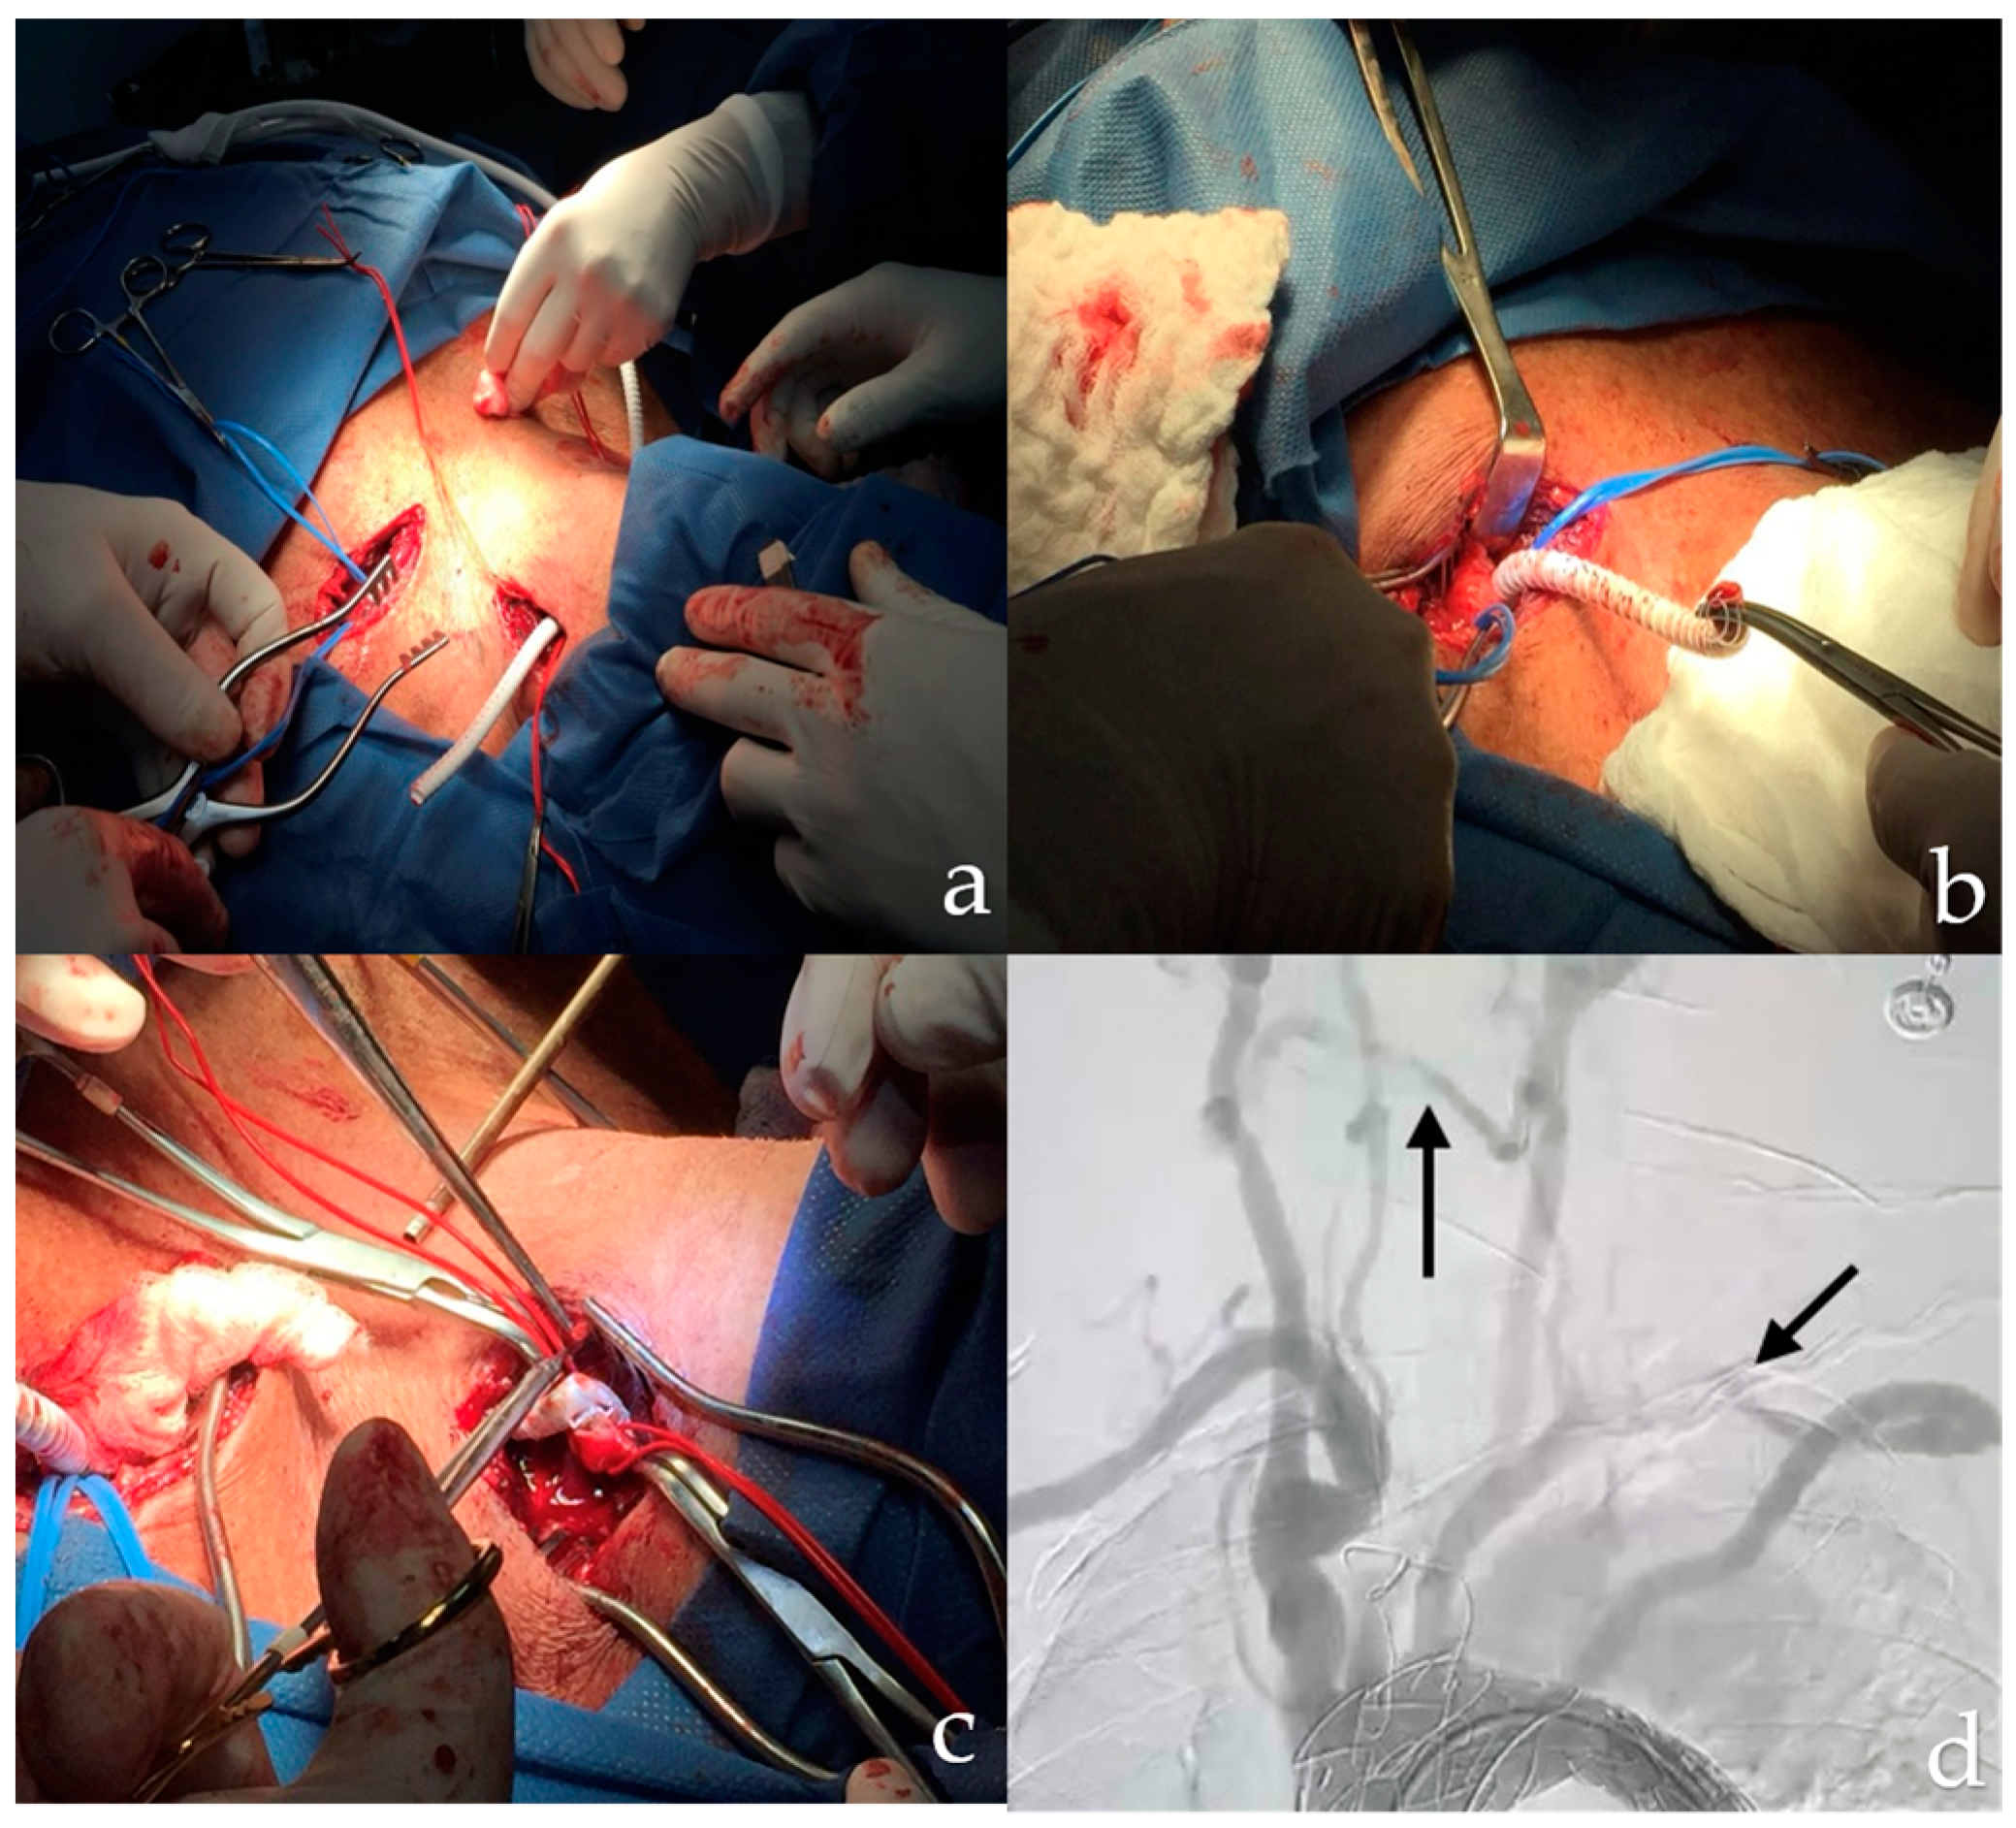

2. Detailed Case Description